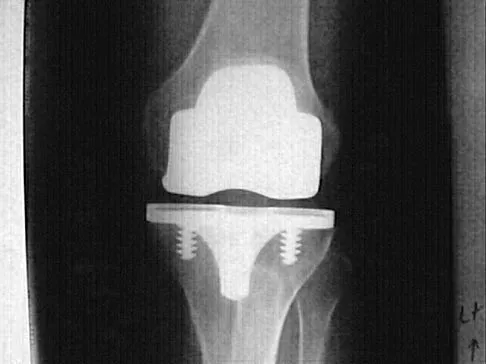

Figure 9 shows the radiograph of a 75-year-old woman who reports the sudden onset of disabling medial knee pain. What is the most likely diagnosis?

A 48-year-old woman has knee pain that is worse with weight bearing. She reports no night pain or pain at rest. History reveals that she underwent total knee arthroplasty with cementless components 2 years ago. Examination reveals tenderness along the medial joint line. Figures 12a through 12c show radiographs and a bone scan. What is the most likely cause of the patient's pain?